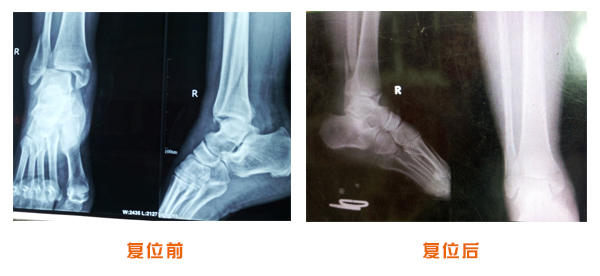

肘關節脫位骨折治療前后對比

踝關節脫位骨折治療前后對比